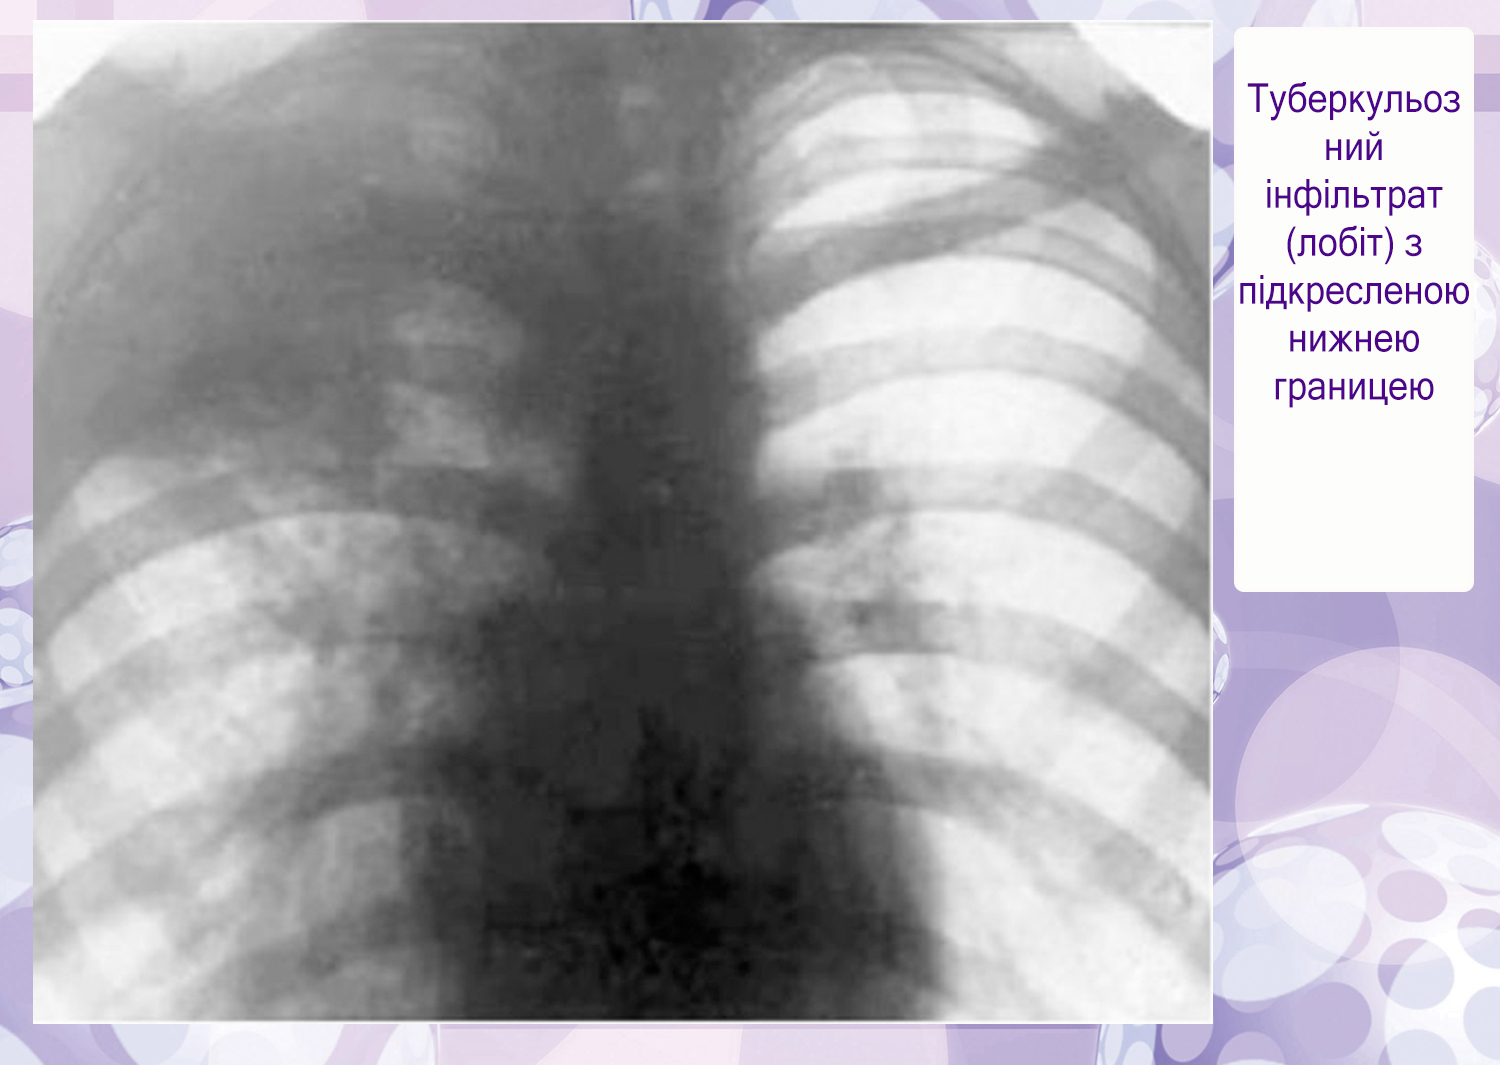

Симптомы и лечение инфильтративного туберкулеза легких

Раздел: Снимки-откровения